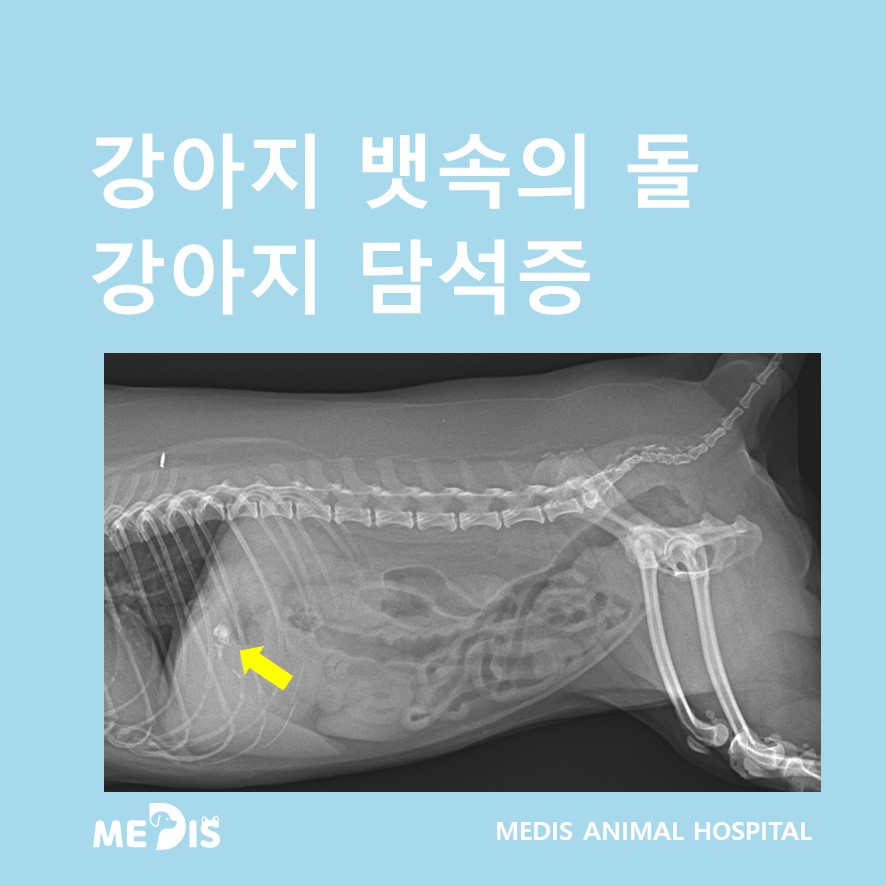

복부 방사선을 촬영했을 때 담낭으로 의심되는 위치에 결석 음영이 관찰되었습니다.